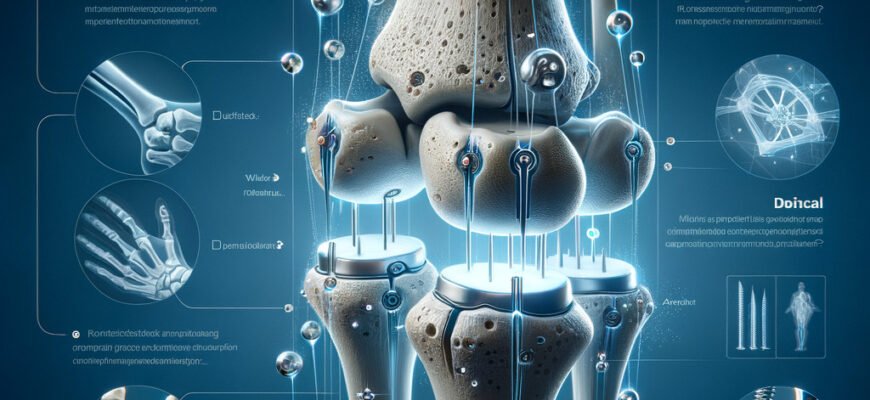

Остеосинтез це метод хірургічного з’єднання фрагментів кістки за допомогою спеціальних інструментів та імплантів. Уявіть собі, як ви збираєте мозаїку — забираєте розбиті частини та з’єднуєте їх так, щоб створити нову цілісність.

- За допомогою пластин: ідеально для поверхневих переломів.

- Внутрішньосуглобова фіксація: з’єднання через середину кістки.

- Зовнішня фіксація: більше для відкритих переломів.

- Штифти та гвинти: для складних переломів та важкодоступних місць.

Матеріали та інструменти

| Нержавіюча сталь | Обробка переломів у зрілому віці |

| Титан | Ідеальний для осіб з алергічними реакціями чи підвищеною чутливістю |

| Карбонові сплави | Висока міцність та легкість |